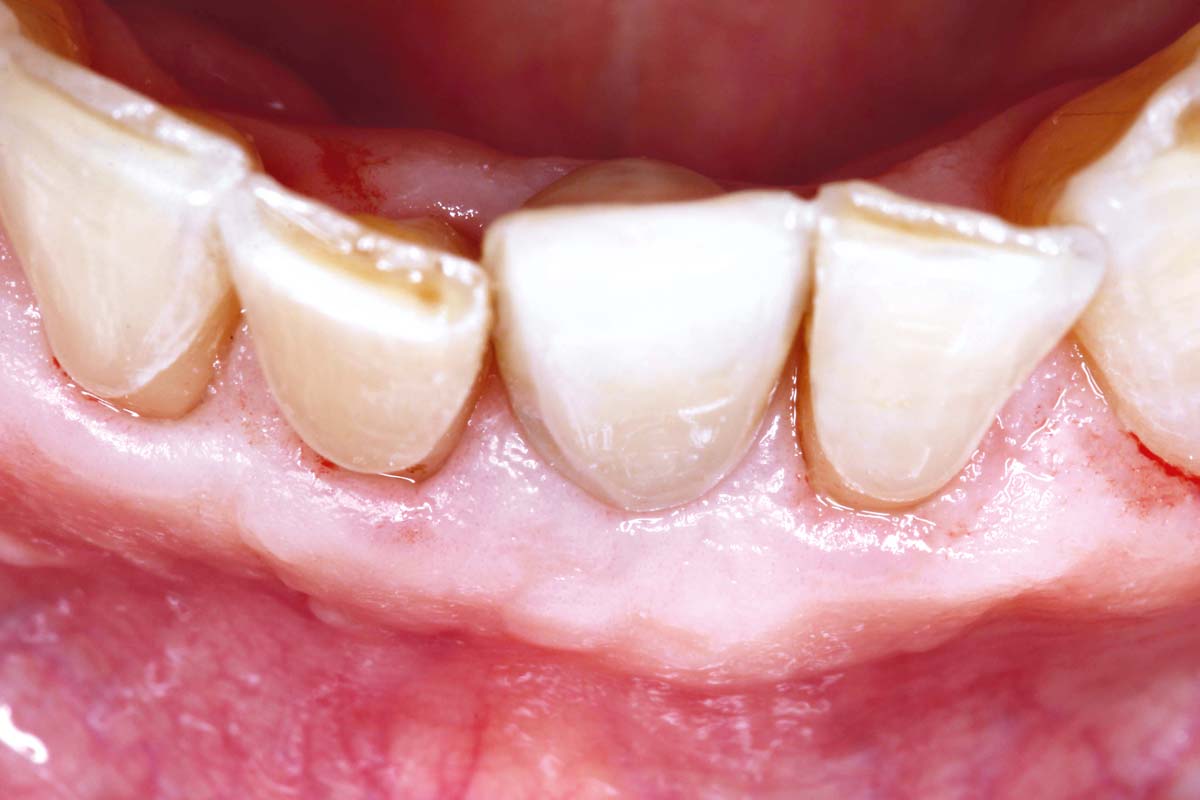

Initial view of the case. Discoloration of 1.1 and mild class I gingival recession